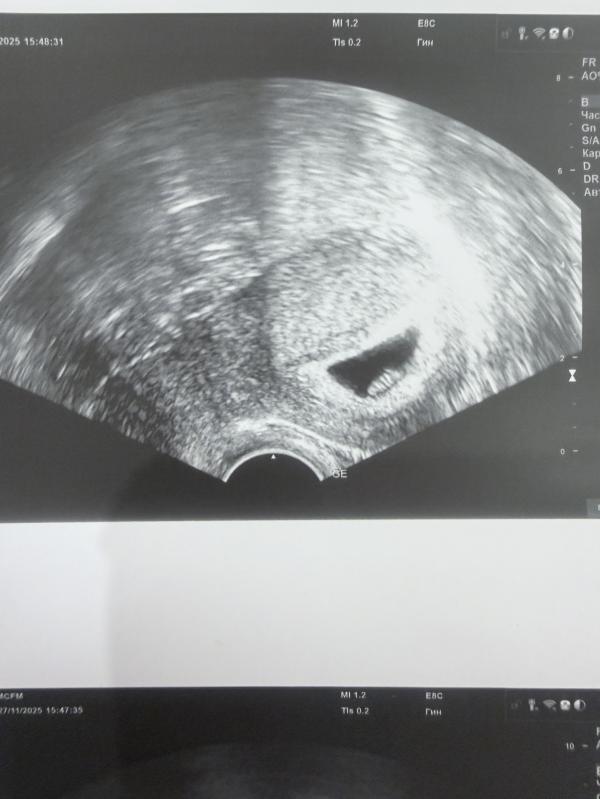

Сегодня день, который я никогда не забуду. Впервые я увидела своего малыша на экране узи, увидела его бьющееся сердечко. Девочки, это непередаваемое ощущение 🙏🏻 я буду молиться каждый день, чтобы этот малыш вырос здоровым и в середине лета мы с ним встретились 🤞🏽🙏🏻

Моя бусинка 🐣